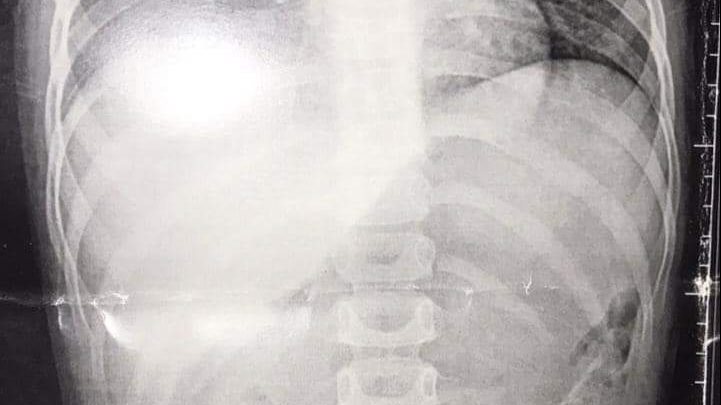

تمكن فريق طبي بقسم جراحة القلب والصدر بمستشفى بنها الجامعي من إنقاذ طفلة تبلغ من العمر سنتين ونصف ابتلعت خرزة شخشيخة أطفال واستقرت في القصبة الهوائية وجرى استخراجها.

وكانت الطفلة تلعب بشخشيخة أطفال ففتحتها وبلعت إحدى الخرزات عن طريق الخطأ فنزلت إلى القصبة الهوائية وأدت إلى انسداد مجرى التنفس.